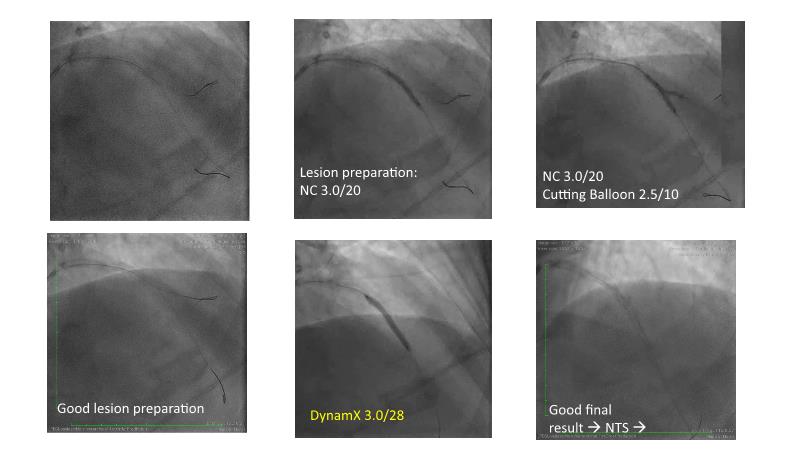

Join this session to explore the revolutionary Dynamx Bioadaptor and its role in restoring vessel physiology and function. Learn about the specific patient and lesion characteristics that can be safely and effectively treated with this innovative device, gain confidence in the delivery and deployment techniques, understand its unique design characteristics and explore the evidence supporting the benefits of vessel restoration.

- To know the patients and lesions that can be safely and effectively treated with Dynamx Bioadaptor

- To be able to approach the delivery and deployment of the Dynamx Bioadaptor with confidence

- To understand the unique design characteristics of Bioadaptor and evidence supporting vessel restoration benefit